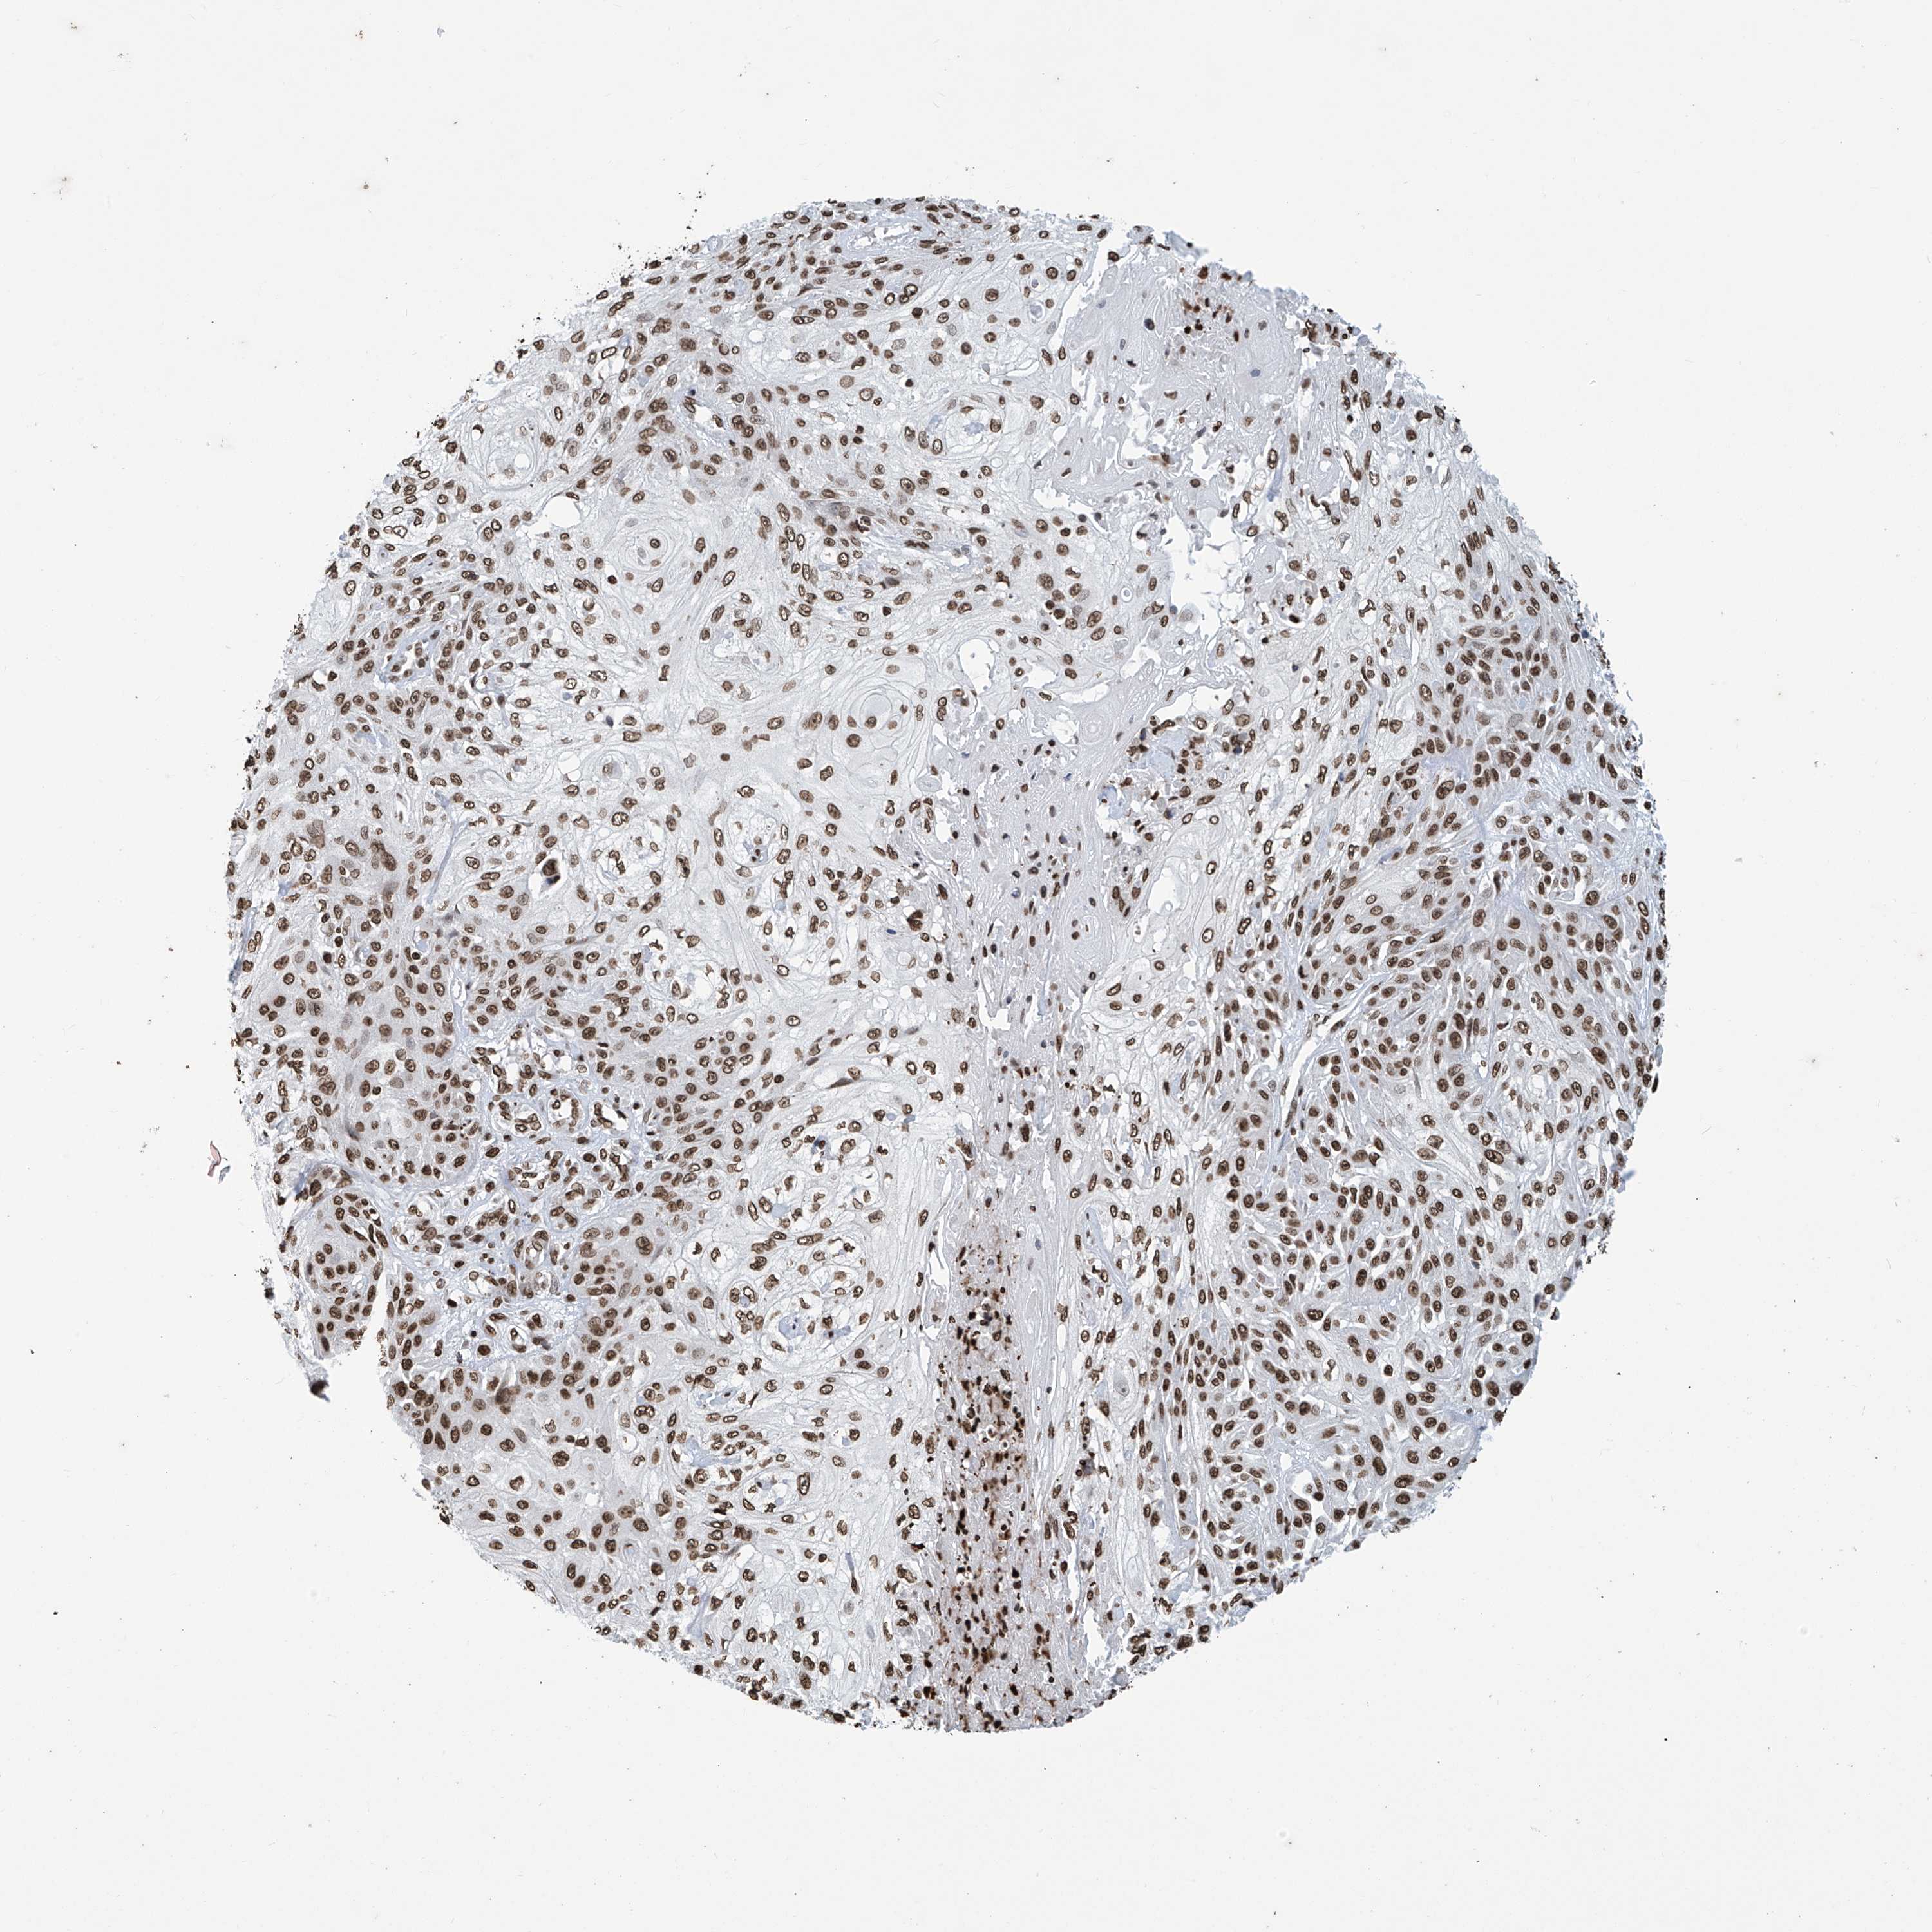

SKIN CANCER - Protein expressioni

A mouse-over function shows sample information and annotation data. Click on an image to view it in a full screen mode. Samples can be filtered based on level of antibody staining by selecting one or several of the following categories: high, medium, low and not detected. The assay and annotation is described here.

Antibody stainingi

Antibody staining in the annotated cell types in the current human tissue is reported as not detected, low, medium, or high, based on conventional immunohistochemistry profiling in selected tissues. This score is based on the combination of the staining intensity and fraction of stained cells.

Each image is clickable and will lead to virtual microscopy that enables deeper exploration of all samples and also displays staining intensity scores, fraction scores and subcellular localization as well as patient and tissue information for each sample.

Antibody HPA036134

Staining

High

Intensity

Strong

Quantity

>75%

Location

Nuclear

Basal cell carcinoma